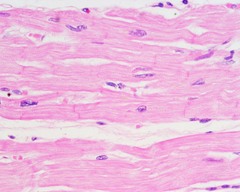

cardiac muscle

found only in the heart

intercalated discs

specialized intercellular junction that connects one cell to another

branched with one nucleus

cardiac muscle the fibers are what?

involuntary

Is cardiac muscle voluntary or involuntary?